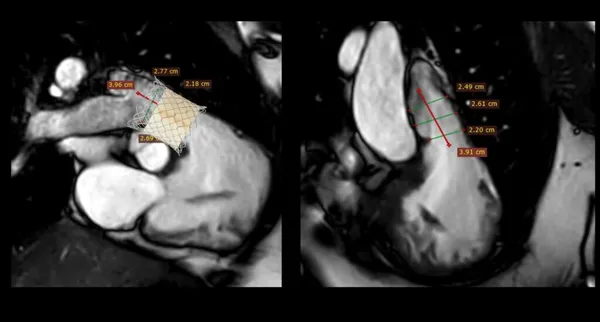

การใส่ลิ้นหัวใจพัลโมนิกเทียมผ่านสายสวนหัวใจ (Transcatheter pulmonary valve implantation; TPRI ) ในครั้งนี้ ทำผ่านทางหลอดเลือดดำใหญ่ บริเวณขาหนีบ จึงไม่ต้องผ่าตัดเปิดทรวงอก โดยกระบวนการรักษาและพักฟื้นผ่านไปได้ด้วยดี ไม่พบภาวะแทรกซ้อน ผู้ป่วยสามารถออกจากโรงพยาบาล 2 วันภายหลังการรักษา นับเป็นหนึ่งในความก้าวหน้าของนวัตกรรมการแพทย์เพื่อใช้รักษา ลดความเสี่ยงของภาวะแทรกซ้อนต่างๆ รวมถึงยกระดับคุณภาพชีวิตของผู้ป่วยได้

การแก้ไขลิ้นหัวใจพัลโมนิกรั่วมี 2 วิธี คือ การผ่าตัดเปิดทรวงอกเพื่อใส่ลิ้นหัวใจพัลโมนิกเทียม และ การใส่ลิ้นพัลโมนิกผ่านทางสายสวนหัวใจ การเปลี่ยนลิ้นทั้งสองวิธีนี้เมื่อเวลาผ่านไป 10-20 ปี ลิ้นพัลโมนิกเทียมจะมีโอกาสเสื่อมอีก ทำให้ผู้ป่วยประมาณ 1 ใน 3 จำเป็นต้องเปลี่ยนลิ้นหัวใจซ้ำอีกครั้ง ซึ่งในผู้ป่วยบางรายอาจจะต้องการการใส่ลิ้นพัลโมนิกเทียมไม่ว่าจะโดยการผ่าตัดหรือผ่านทางสายสวน 2-3 ครั้งในช่วงชีวิตหนึ่ง

การผ่าตัดเปิดทรวงอกในแต่ละครั้ง จะก่อให้เกิดพังผืด (fibrous adhesion) เพิ่มความยากลำบาก และความเสี่ยงในการผ่าตัดมากขึ้น การรักษาผ่านทางสายสวนจึงเป็นทางเลือกที่จะลดความเสี่ยงนี้ลง อีกทั้งยังสามารถใส่ลิ้นพัลโมนิกเทียมชิ้นใหม่ทับแทนชิ้นเก่าได้ (valve in valve procedure)